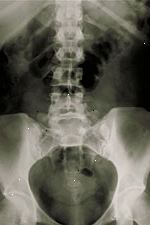

Bederní X-ray

X-paprsky páteře může být provedeno vyhodnocení jakékoli oblasti páteře (krční, hrudní, bederní, křížové, nebo kokcygeální). Další související postupy, které mohou být použity pro diagnostiku páteř, záda, nebo problémy s krční patří myelografie ( myelogram ), počítačová tomografie (CT), magnetická rezonance (MRI), nebo kostní skeny. Viz následující postupy pro další informace.

Když tělo prochází x-paprsky, různé části těla, aby různé množství rentgenových paprsků projít. Snímky jsou vyráběny ve stupních světla a tmy, v závislosti na množství rentgenových paprsků, které pronikají do tkáně. Měkkých tkání v těle (např. krev, kůži, tuku a svalů), aby většina z rentgenu projít a objevují tmavě šedá na filmu. Kosti nebo nádor, který je hustší než měkkých tkání, umožňuje několik x-paprsky projít a objeví bílé na x-ray. Při přerušení v kosti, x-ray paprsek prochází rozbité oblasti a jeví se jako tmavé čáry na bílé kosti.